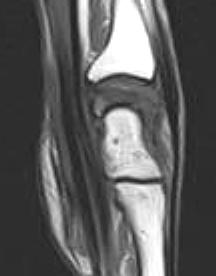

Stage IV:

There is degenerative arthrosis of the lunate and carpus. Hyperintense areas are not seen on the T2W, GRASS or STIR images and lunate collapse can be seen in all planes. Splaying of the volar and dorsal poles of the lunate is accompanied by extrinsic effacement and convex bowing of the flexor tendons in the sagittal plane. This may contribute to symptoms of carpal tunnel syndrome, especially if there is associated proximal migration of the flexor retinaculum with wrist shortening. Fragmented portions of the lunate usually demonstrate low signal intensity on T1W and GRASS images. Synovitis and radiocarpal effusion may be seen. Pannus tissue is low to intermediate in signal intensity on T1W and T2W images and enhances with gadolinium intravenous contrast. There may be wrist arthrodesis.